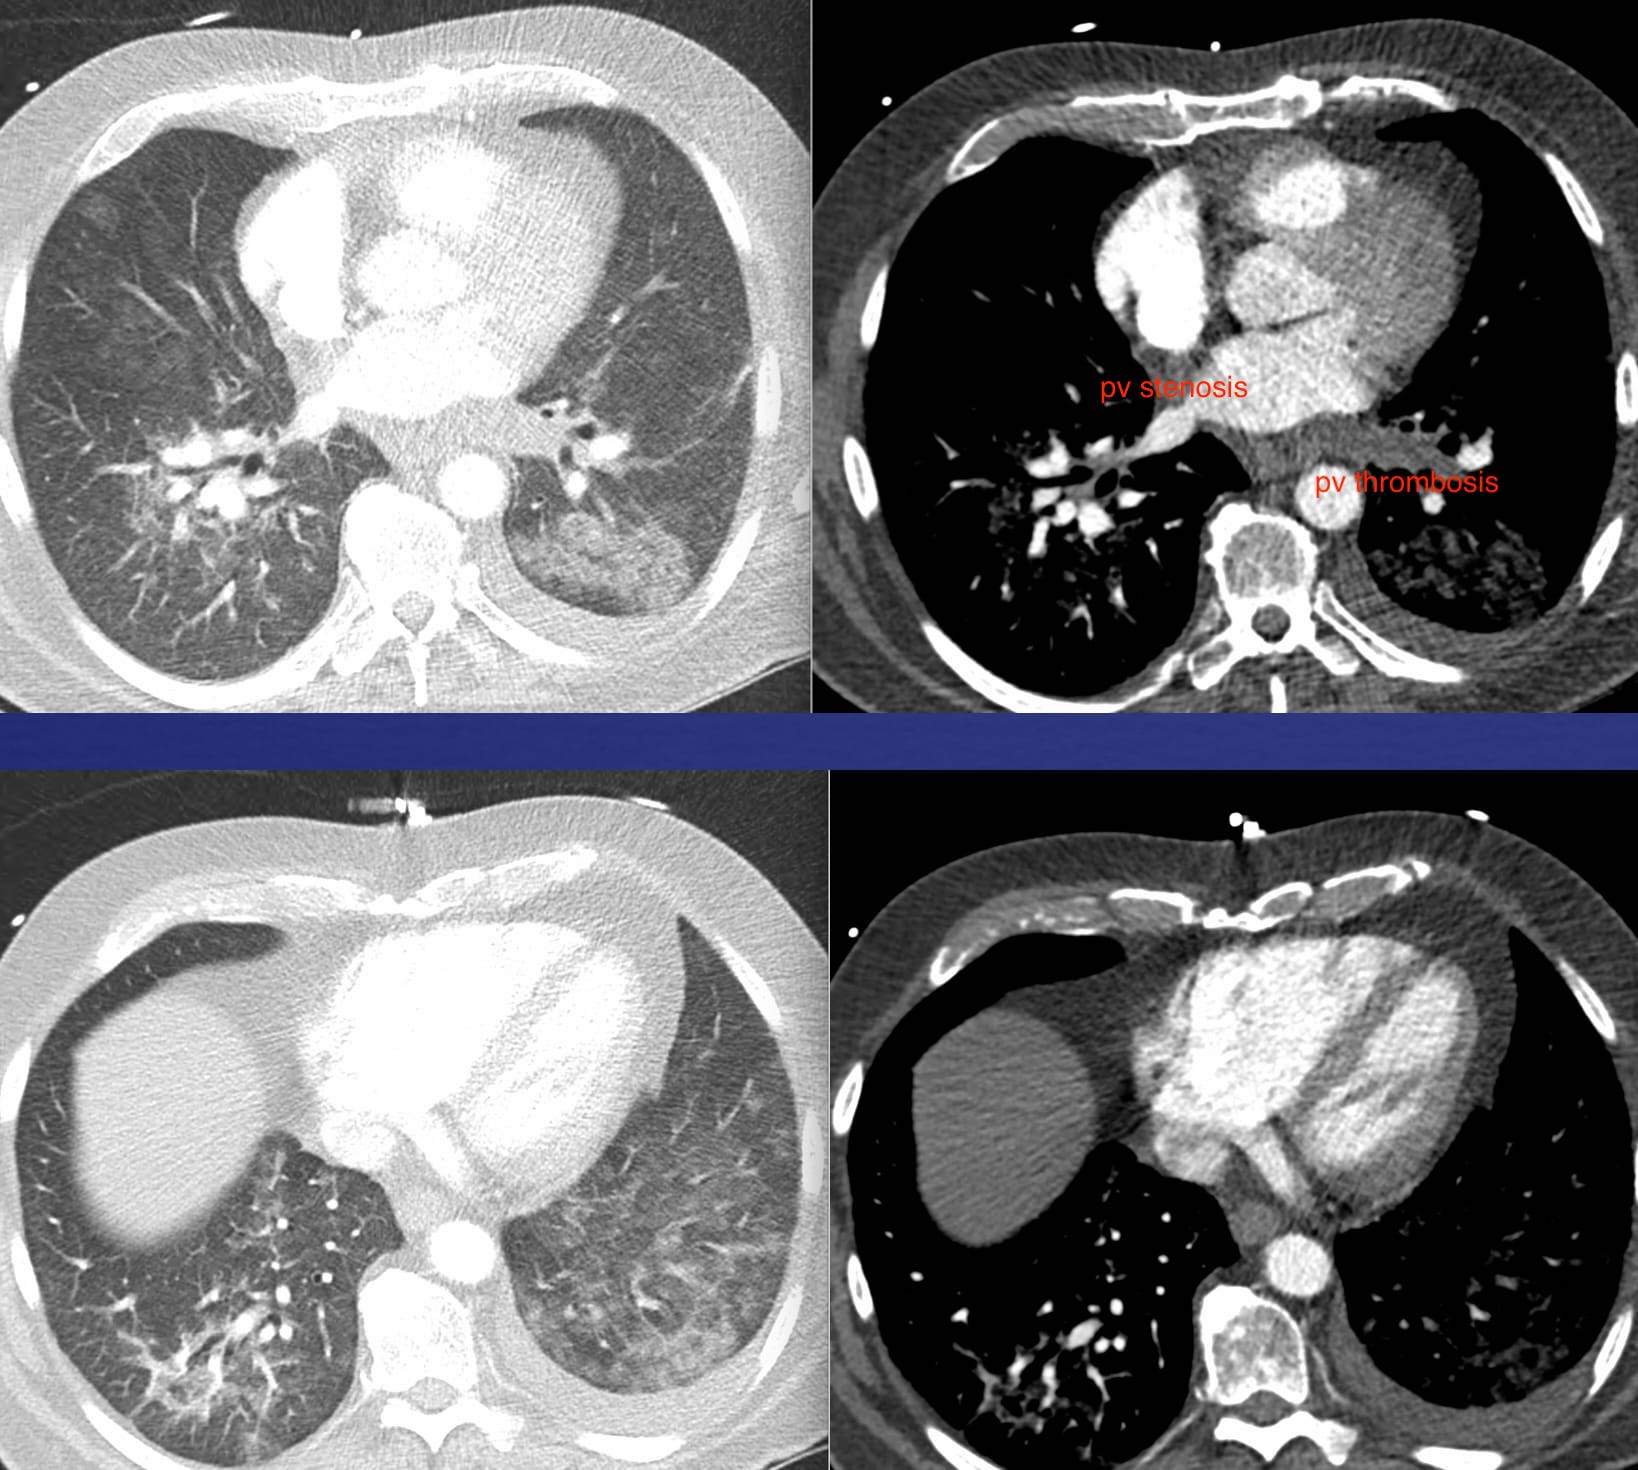

Lung Edema in Pulmonary Venous Occlusions

Narrowing and occlusions of veins—large and small—may produce lung edema.

The edema may be diffuse or focal depending on the cause and location.

Here are three illustrative cases.

Chronic edema, mostly in the left lower lobe, a consequence of a radiofrequency ablation procedure for atrial fibrillation.

A patient diagnosed with pulmonary arterial hypertension (normal pulmonary artery occlusion pressure).

Findings: Diffuse, bilateral interstitial edema.

Diagnosis: Pulmonary veno-occlusive disease–affecting small pulmonary veins.